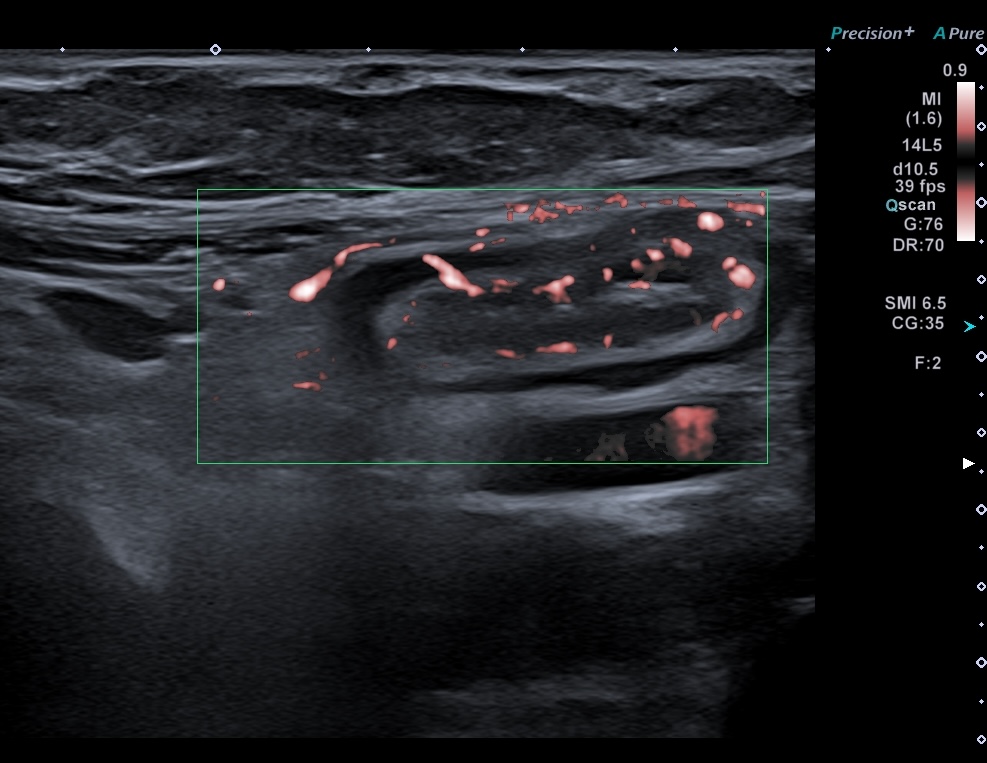

Doppler +

En cas d'inflammation, on peut voir 4 types de modifications échographique: